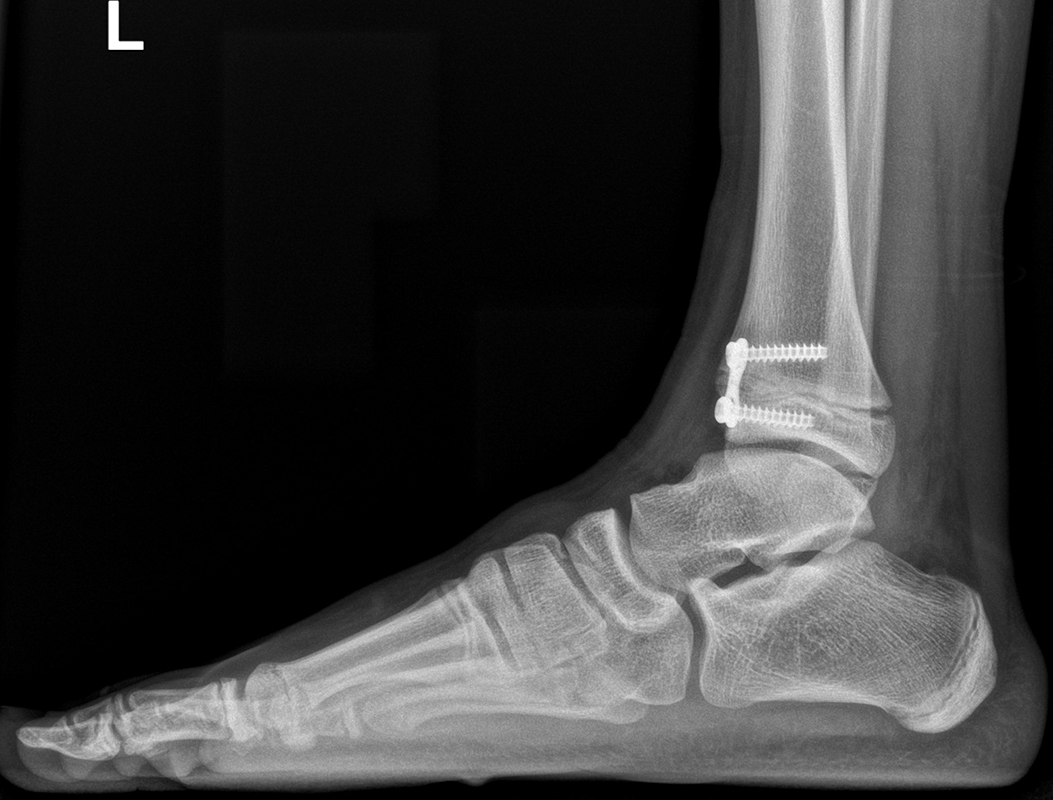

Knick-Senk-Platt-Fuß Korrektur mit dem Canalis Tarsi Spacer

In der Korrektur des schmerzhaften, aber flexiblen Knick-Senk-Fußes oder Plattfußes ist die Schraubenarthrorise mit einem Sinus tarsi oder besser bezeichnet als Canalis tarsi Spacer und alternativ mit einer Calcaneus-Stopp-Schraube seit vielen Jahren ein etabliertes Verfahren und führt zu einer kompletten Korrektur von flexiblen Knick- und Plattfuß-Fehlstellungen (Abb. 7). Die nötige Schnittlänge über dem Sinus tarsi beträgt für beide Verfahren 1 cm.